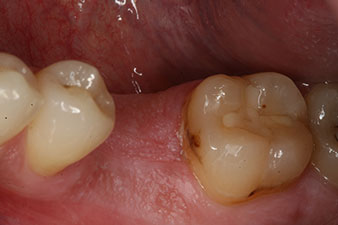

En el paciente de 28 años con un historial de fumador severo, fue preciso extraer la pieza dental 36 como consecuencia de una recidiva de una periodontitis apical.

Como las piezas dentales adyacentes estaban en su mayoría intactas, el único tratamiento posible para los huecos existentes era un implante.

No obstante, seis semanas después de la extracción, tras la disección del colgajo mucoperióstico, se observó una osificación incompleta en el área del antiguo alvéolo mesial.